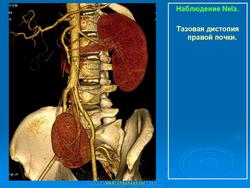

Тазовая дистопия почки

Такая аномалия встречается не часто. При этом почка находится в малом тазу. Обычно между мочевым пузырем и прямой кишкой у мужчин и маткой и прямой кишкой у женщин. При этой аномалии жалобы у пациента связаны с нарушением функции органов, соседствующих с аномально расположенной почкой. Возникают боли в прямой кишке, иногда запоры, боли во время полового акта у женщин и т.д. Иногда такую почку обнаруживают при гинекологическом исследовании, как плотное образование позади заднего свода влагалища, или при пальцевом исследовании прямой кишки.